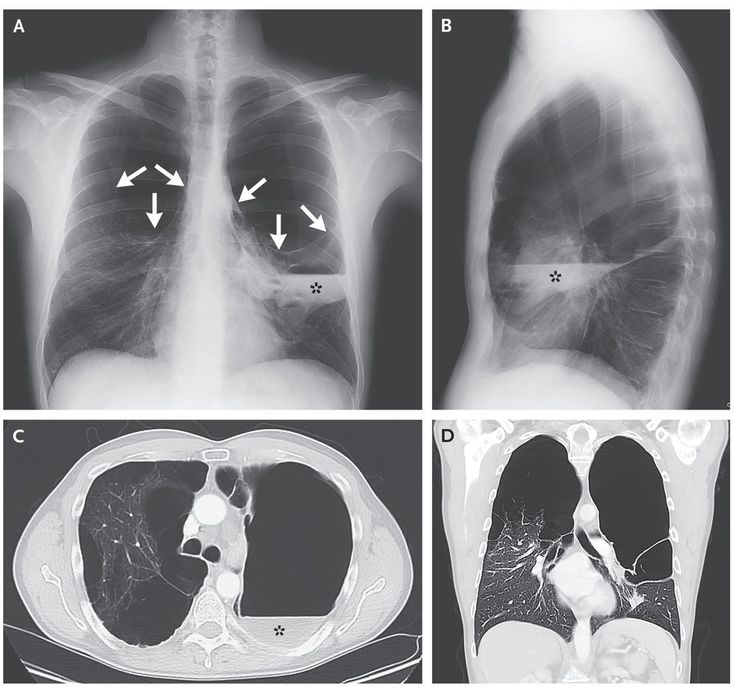

A 41-year-old man with a smoking history of 30 pack-years presented with chronic chest pain, dyspnea, and cough. His vital signs were normal, and laboratory studies were unremarkable, including his level of α1-antitrypsin, which was normal. Physical examination revealed cachexia, with decreased apical breath sounds and hyperresonance to percussion in both lungs. Chest radiography showed extensive bullous lung disease in the apex and upper lobes of both lungs (Panel A, arrows; Panel B), which was suggestive of vanishing lung syndrome; air–liquid levels were seen in the left lung (Panels A, B, and C, asterisk). Computed tomography of the chest confirmed these findings (Panels C and D). Vanishing lung syndrome, otherwise known as idiopathic giant bullous emphysema, typically occurs in young, thin male smokers. The radiographic criteria for vanishing lung syndrome were proposed in 1987, and they include giant bullae in one or both upper lobes occupying at least one third of the hemithorax and compressing surrounding parenchyma. Air–liquid levels within bullae are uncommon and raise the question of bacterial superinfection. Lung-volume–reduction surgery is considered for selected patients with vanishing lung syndrome after assessment of exercise capacity, pulmonary-function testing, and smoking cessation. This patient underwent successful lung-volume–reduction surgery and is currently without residual symptoms.